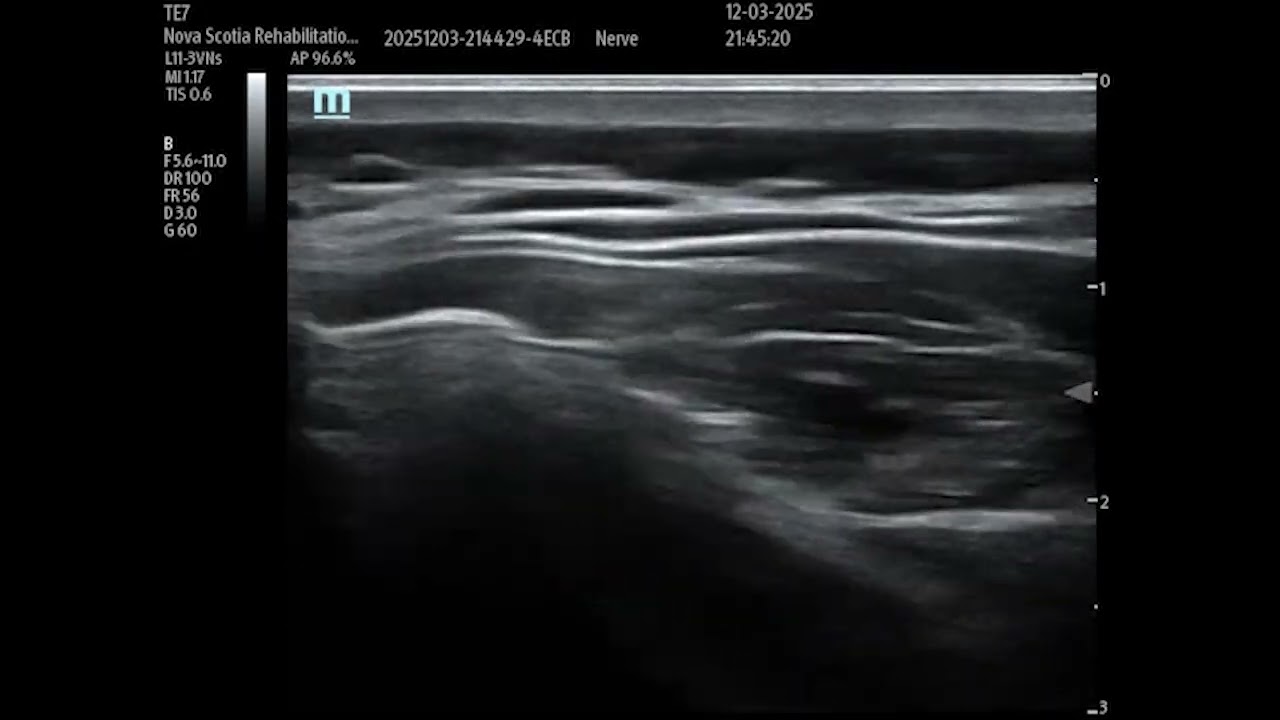

Инъекции под контролем УЗИ при цервикальной дистонии: грудино-ключично-сосцевидная мышца и лестни...

Описание: Инъекции под контролем УЗИ при цервикальной дистонии: грудино-ключично-сосцевидная мышца и лестничные мышцы